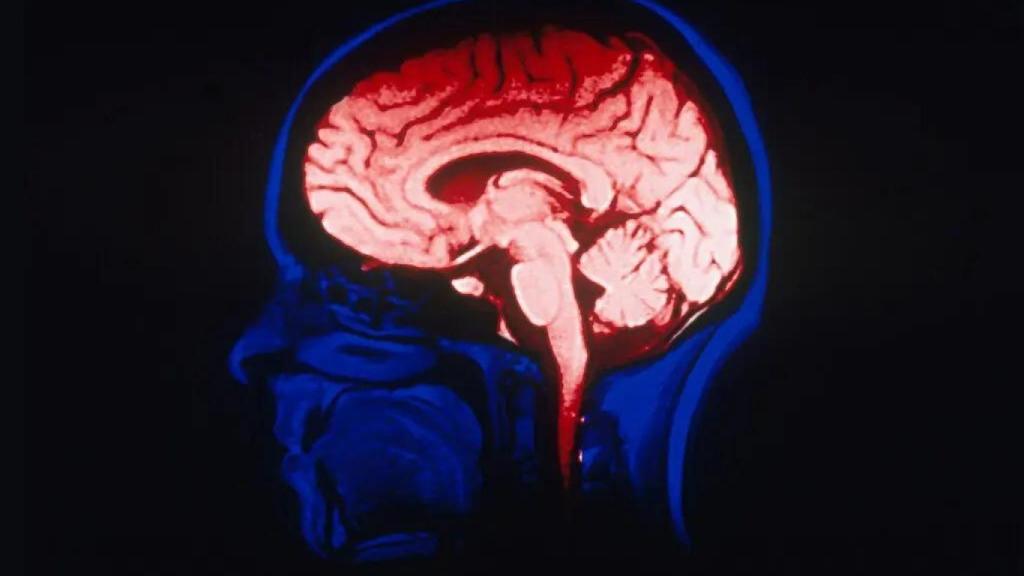

Miles de millones de euros, cientos de científicos y Obama: así es el proyecto BRAIN para descifrar el cerebro humano

Investigadores de todo el mundo participan en una iniciativa sin precedentes que pretende entender trastornos como el autismo o la esquizofrenia.

La iniciativa BRAIN, lanzada por Barack Obama en 2013, ha impulsado una inversión de más de 6.000 millones de dólares para descifrar el funcionamiento del cerebro humano.

En abril de 2013, Barack Obama tal vez uno de los presidentes que mayor impulso dio a la ciencia en Estados Unidos subió al estrado de la Casa Blanca para presentar una de las apuestas científicas más ambiciosas de este siglo.

Inspirado por el proyecto que descifró el genoma humano, Obama anunció la iniciativa BRAIN (Brain Research through Advancing Innovative Neurotechnologies), una hoja de ruta para desentrañar el órgano más complejo del cuerpo.

El objetivo sonaba utópico: mapear la actividad de cada célula y cada conexión neuronal. Diez años después, aquel impulso político y económico —más de 6.000 millones de dólares (unos 5.200 millones de euros) invertidos hasta la fecha— ha dado lugar a una revolución científica global.